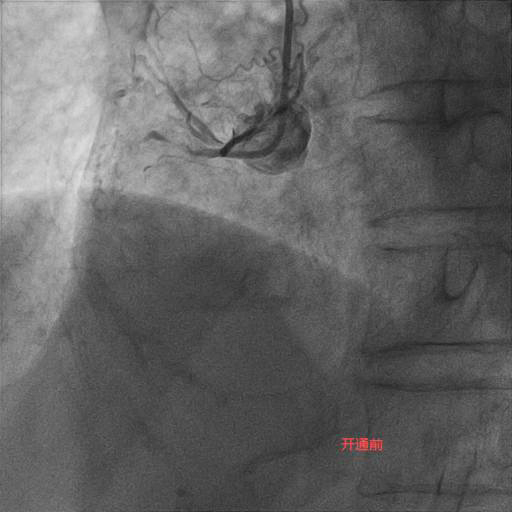

李奶奶今年92岁高龄,两年前曾因“急性心肌梗死”就诊于某医院,接诊专家考虑患者年龄大,合并症多,冠状动脉介入操作风险高,建议药物治疗。近半个月,李奶奶的胸痛症状频繁发作,药物治疗效果不佳,经过病友的介绍,家属选择了潞河医院翟光耀主任团队。在心脏监护室医护人员的精心治疗和护理下,李奶奶心功能改善,肺部感染得到控制,可以耐受手术。术中,冠状动脉造影显示LAD弥漫重度狭窄,RCA完全闭塞伴重度钙化。在经过近两个小时的不断尝试及努力后,闭塞的RCA成功开通,“介入无植入”未植入支架,血管成功修复。术后李奶奶恢复良好,顺利出院。